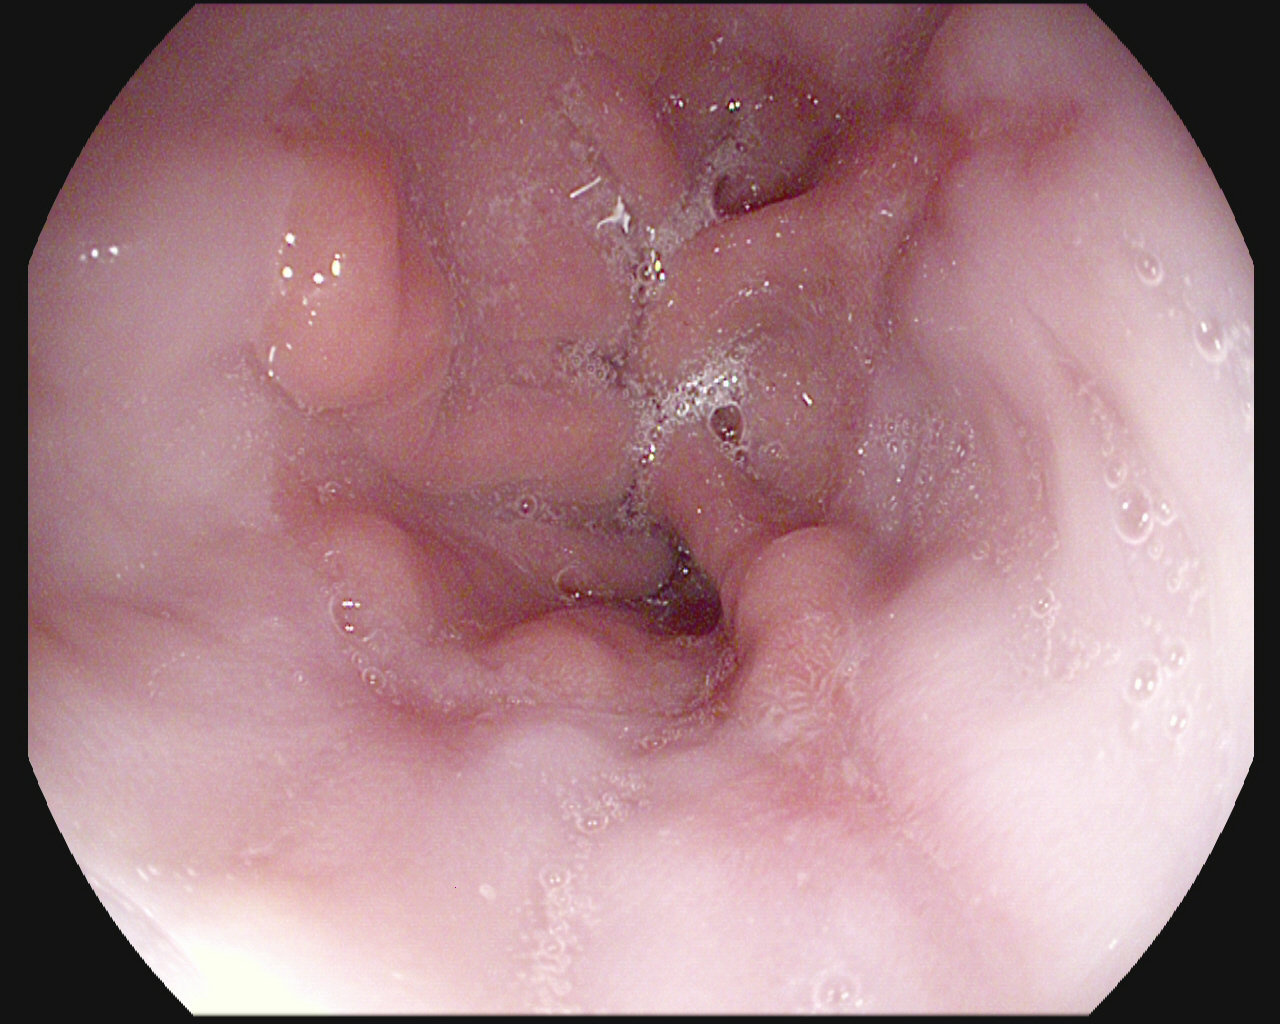

The Kvasir Dataset

Dyed lifted polyps

Dyed resection margins

Polyps

Ulcerative colitis

Normal cecum

Esophagitis

Normal z-line

Normal pylorus